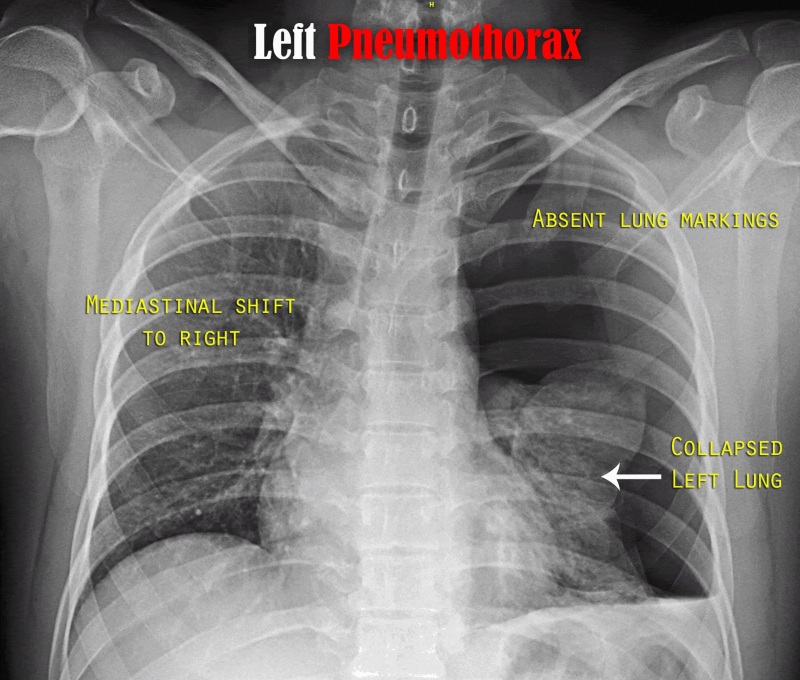

Q.41. The best early sign to detect tension pneumothorax is?

Correct Answer : A

In tension pneumothorax, trapped air in the pleural space builds pressure and pushes the mediastinum, and trachea away from the affected side.

- All other options are a late sign.